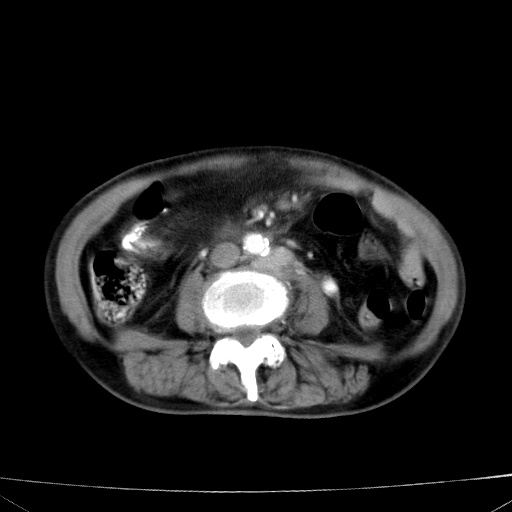

网站人气太旺!昨天的帖子就沉到海底,只好再发贴!ct18338:女 78岁,肝胆病变,已增强,再会诊!原帖链接:http://www.radida.com/bbs/forum.php?mod=viewthread&tid=50032

1)考虑胆囊癌侵犯肝脏并肝门区、腹膜后及右侧膈角后淋巴结转移。2)肝左叶近肝顶部囊肿。3)肝左叶肝内胆管结石。4)左肾近下极囊肿。